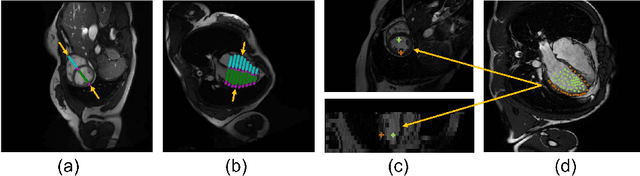

Abstract:Combining information from multi-view images is crucial to improve the performance and robustness of automated methods for disease diagnosis. However, due to the non-alignment characteristics of multi-view images, building correlation and data fusion across views largely remain an open problem. In this study, we present TransFusion, a Transformer-based architecture to merge divergent multi-view imaging information using convolutional layers and powerful attention mechanisms. In particular, the Divergent Fusion Attention (DiFA) module is proposed for rich cross-view context modeling and semantic dependency mining, addressing the critical issue of capturing long-range correlations between unaligned data from different image views. We further propose the Multi-Scale Attention (MSA) to collect global correspondence of multi-scale feature representations. We evaluate TransFusion on the Multi-Disease, Multi-View \& Multi-Center Right Ventricular Segmentation in Cardiac MRI (M\&Ms-2) challenge cohort. TransFusion demonstrates leading performance against the state-of-the-art methods and opens up new perspectives for multi-view imaging integration towards robust medical image segmentation.